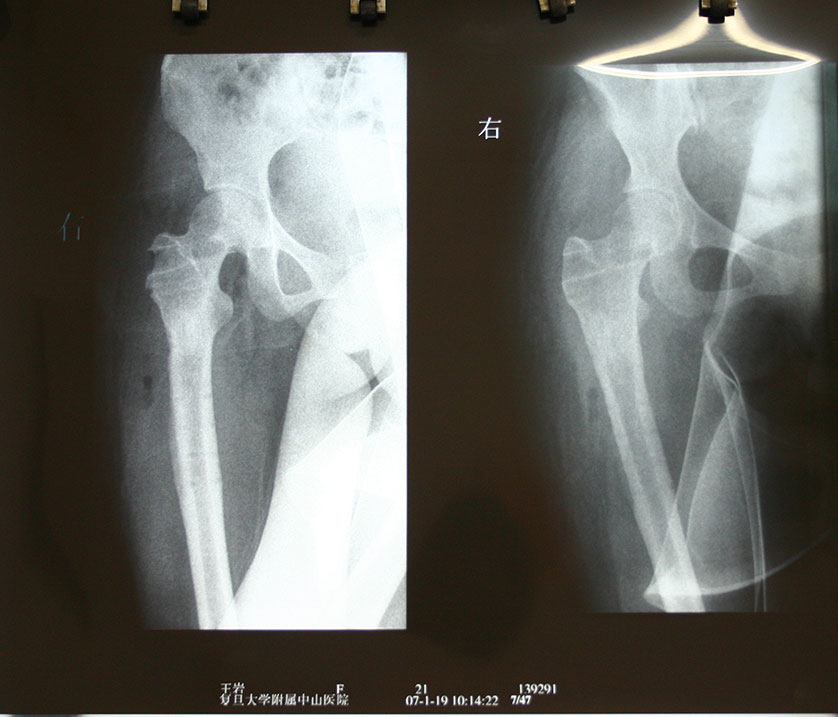

王*,女性,因右股骨骨囊肿,于2005年11月行囊肿刮除,同种异体骨颗粒植入,股骨近端DHS钢板螺钉内固定术后,术后1年和2年随访,骨愈合良好,内固定拔除。